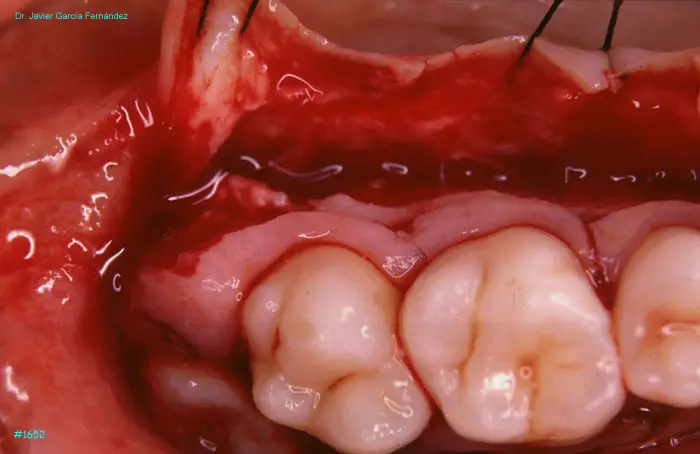

Atlas of Surgical Techniques in Periodontics. Chapter IV. Atlas de Técnicas Quirúrgica en Periodoncia

image 165